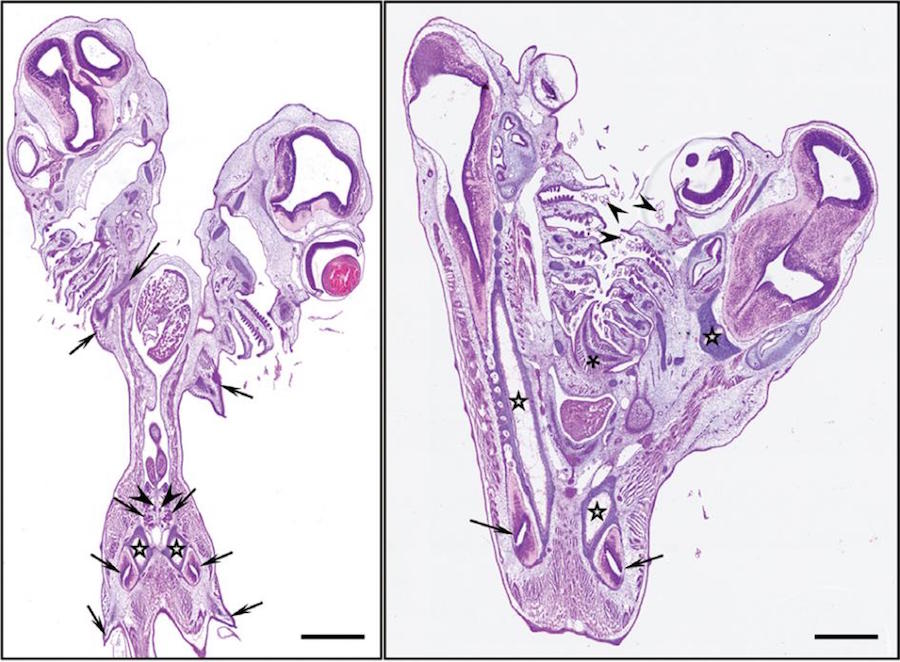

Recientemente los científicos de la Universidad de Málaga estaban estudiando el sistema cardiovascular en una especie de tiburones gato (Galeus atlanticus) ubicada en la costa noroeste de Marruecos, cuando encontraron un ejemplar de estos con dos cabezas.

Puede que para ustedes no suene como nada fuera de este mundo, pero si tomamos en cuenta la publicación de National Geographic, es como nos damos cuenta de que esta es la primera vez que la ciencia ha registrado el caso de un espécimen bicéfalo en un tiburón ovíparo.

Las causas de que esto se presente en esas criaturas aún son desconocidas, pero equipo de científicos -liderado por el Profesor Valentín Sans-Coma- sospechan que la genética podría ser la principal culpable, negando así que cualquier factor ambiental pudiera tener que ver.

“Hemos visto tiburones de dos cabezas ocasionalmente”, dijo George Burges, el director de las investigaciones de tiburones en el Museo de Historia Natural de Florida. “Es una anomalía causada por defectos genéticos. Existen diferentes tipos de defectos en los genes y en la mayoría de las ocasiones, los ejemplares que los padecen no logran salir de la matriz de sus madres.